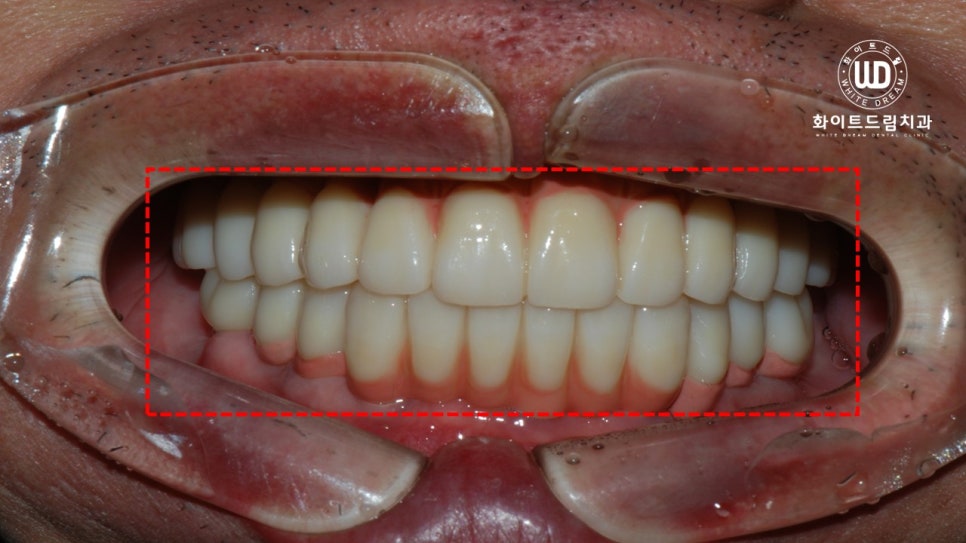

다음은 상악동 거상술과 치조골이식술을 동반한 임플란트 식립 후 최종 진단 결과물입니다.

좌측에 보이는 사진이 임플란트 치료 전 모습이며, 우측이 치료 후 모습입니다.

이전의 구강상태와 확연한 차이를 보이고, 구강 저작력이 크게 향상되는 등 만족스러운 결과가 나왔습니다.

치료가 완료된 사진을 살펴보면 임플란트가 뿌리부터 머리까지 나란히 매끄럽게 연결되어 있는 것을 확인하실 수 있는데, 상악 하악의 U자 형태가 본 케이스와 같이 나올 수 있으려면 임플란트 보철 식립 방향을 잘 체크해야합니다.

환자분께서 부분틀니를 사용하다가 전체 임플란트를 진행하게 됐는데, 훨씬 더 편안하고 음식을 씹는데 큰 문제가 없어 만족한다는 말씀을 전해주신 것이 기억에 남습니다.